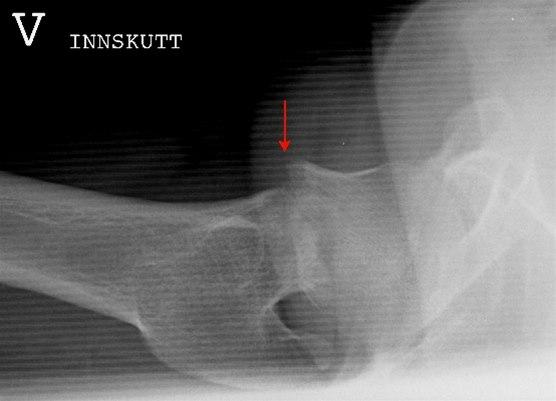

Over halvparten av alle hoftebrudd utgjøres av brudd gjennom lårhalsen, mens brudd i lårbeinsknuten utgjør de fleste av de gjenstående bruddene Brudd i selve skaftet av lårbeinet står kun for omtrent 3% av alle brudd i dette beinet. Bruddene inndeles etter hvor lårbeinet brekker samt undertyper . Bildene under viser lårhalsbrudd og skillet mellom brudd med og uten feilstilling (dislosering).

Ikke alle brudd fører til knekkdannelse mellom de to bruddendene. Det hender også at bruddet fører til at de to beinendene stukes sammen (innkilte brudd) slik at bruddet er forholdsvis stabilt og ikke kommer ut av stilling. Slike brudd kan være vanskelige å se på røntgen.